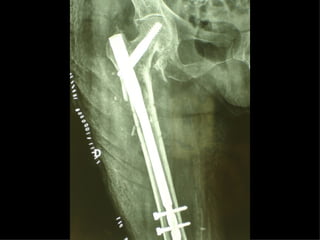

La placca a compressione percutanea (PC.C.P.) di Gotfried è un mezzo di sintesi studiato per assicurare un “impattamento controllato” delle fratture pertrocanteriche grazie alle due viti telescopiche prossimali che garantiscono una ottima stabilità rotazionale

Con la placca di Gotfried non si è mai riscontrato un danno iatrogeno del muro laterale e nessun collasso della frattura.Ciò è dovuto al fatto che i fori per l’applicazione delle due viti prossimali sono di piccolo diametro (9 mm) rispetto ai 16-32 mm necessari per introdurre la vite cefalica di un chiodo endomidollare o di una vite-placca a compressione.

Dal Gennaio 2005 ad Agosto 2006 110  placche di Gotfried Età media  : 78 anni (range 29-94) Tempo chirurgico: 30 minuti (range 12-45) IMMEDIATA CONCESSIONE DEL CARICO